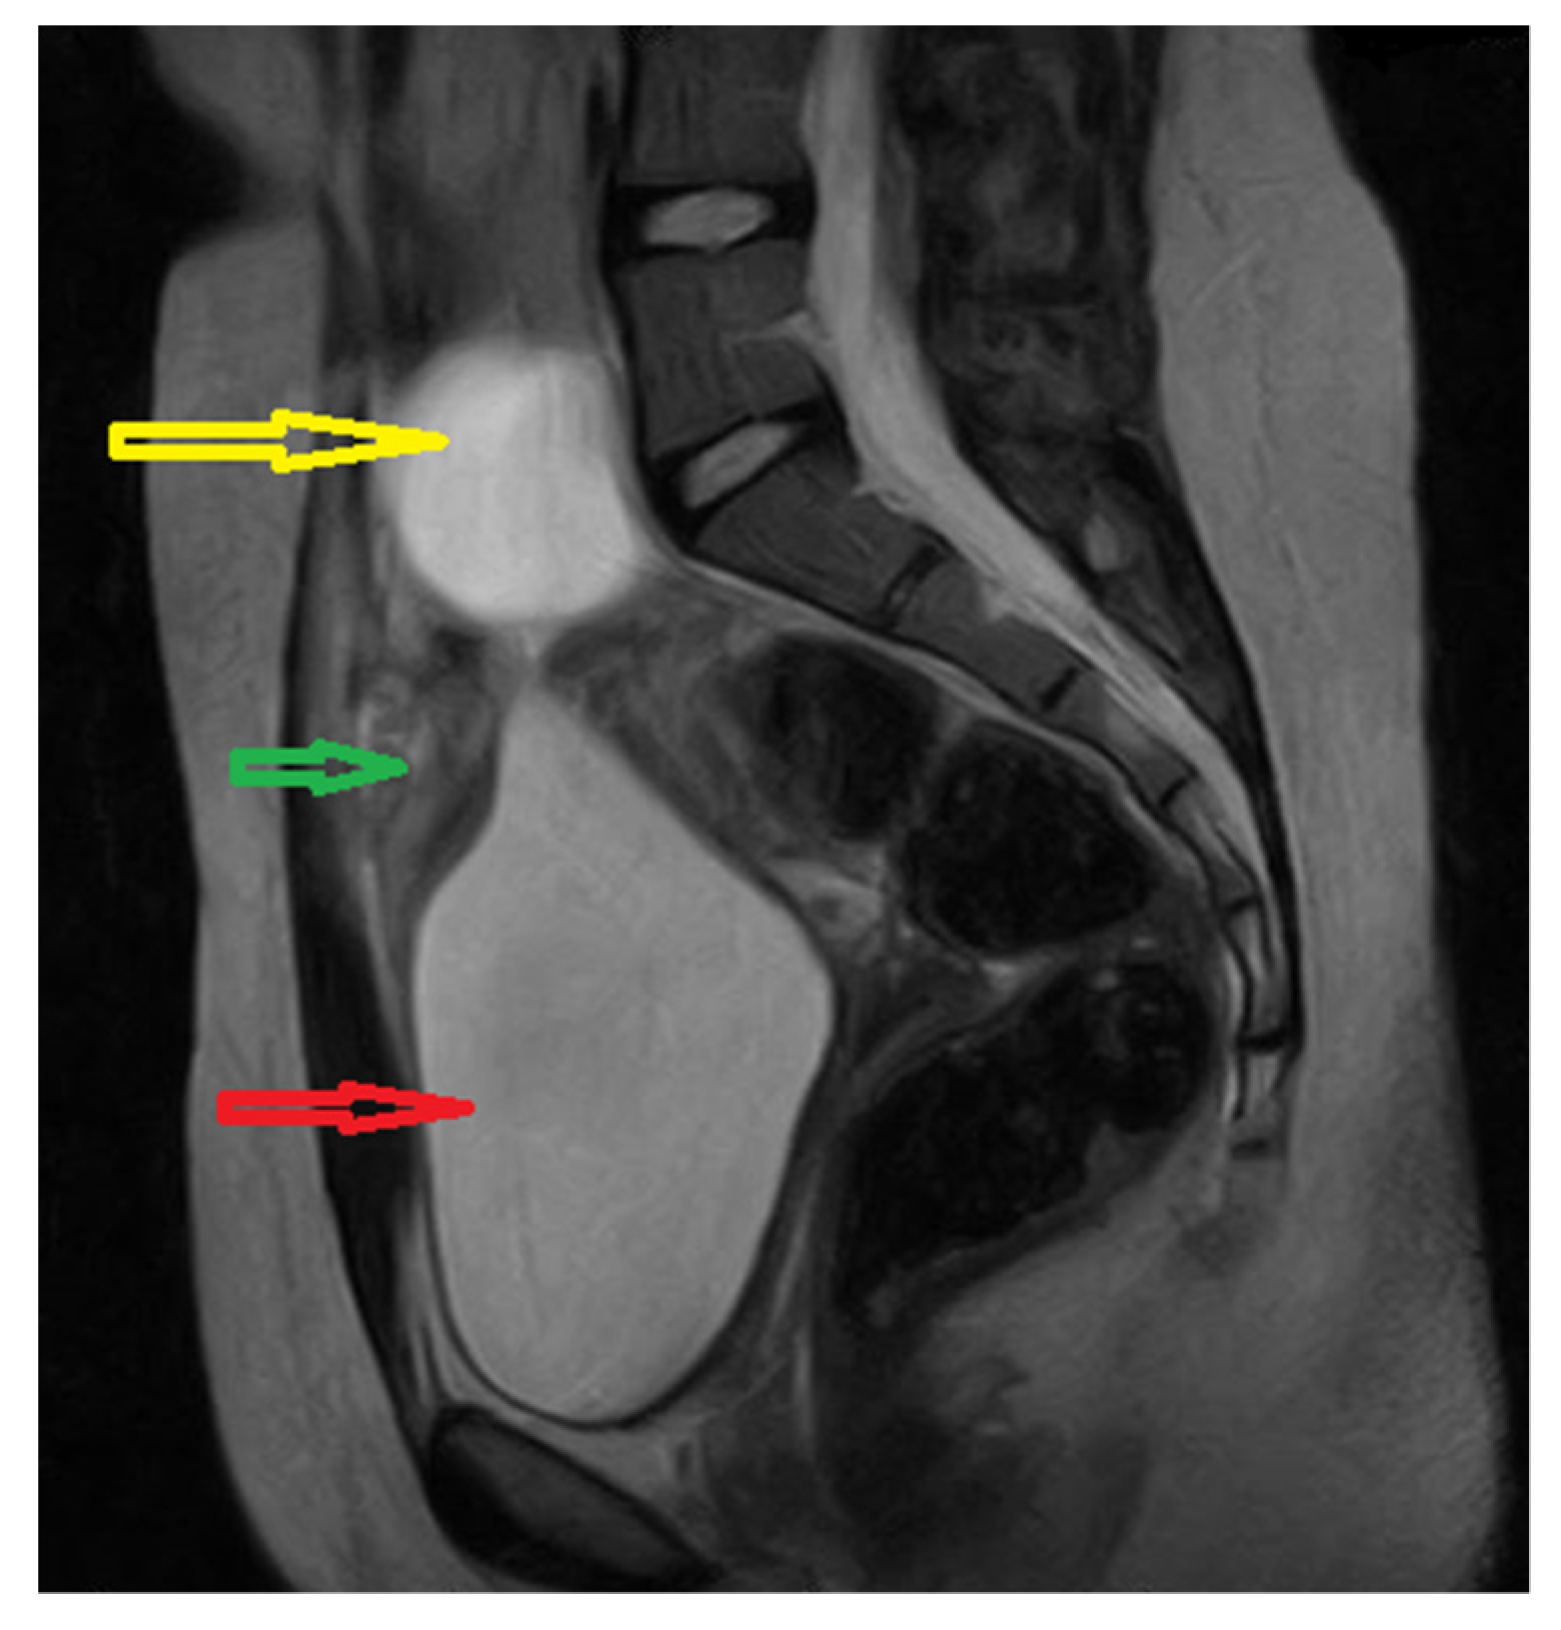

The abdominal ultrasound (US) discovered a 28/21 mm hypoechogenic round tumor in the midline of the hypogastric region, anterosuperior to the bladder and posterior to the abdominal wall, with diffuse mural thickening. The uterus and both ovaries appeared to be normal. We decided to perform a pelvic MRI which showed a 16/18/32 mm inhomogeneous nodular lesion, apparently on the urachal tract; the bladder was in repletion, with mural thickening of the anterosuperior wall. The left ovary presented a 41/34 mm cyst, considered as a hemorrhagic corpus luteum (Figure 1).

Figure 1. Pelvic MRI image: Sagittal T2-weighted yellow arrow: left ovarian cyst; green arrow: supposed urachal cyst; red arrow: urinary bladder.